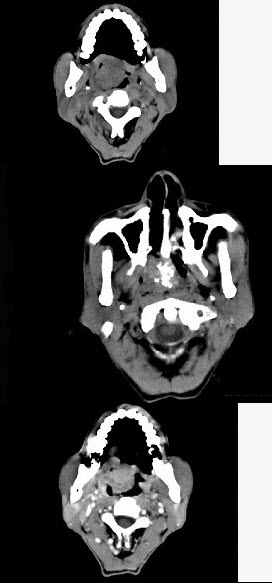

男性,57岁,睡觉打鼾,近来加重,CT扫描如图所示,请选择正确的描述和答案()。

A、鼻咽腔偏右侧可见类圆形软组织块影

B、肿块内密度尚均匀,其上方见较多钙化影

C、肿块边缘大部清楚,邻近结构未见明显受侵

D、考虑为鼻咽癌

E、考虑为鼻咽部多形性腺瘤

A,B,C,E